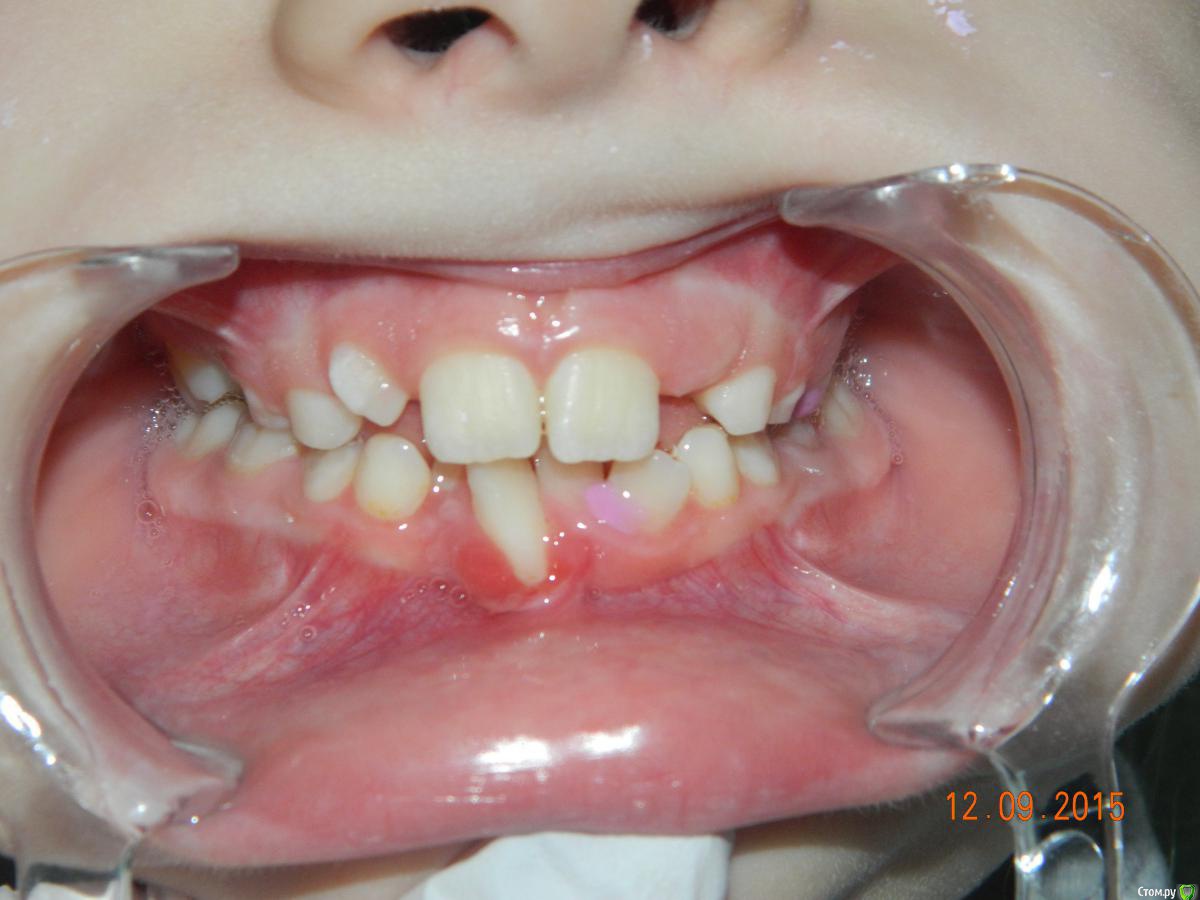

yakinanata Опубликовано 15 сентября, 2015 Поделиться Опубликовано 15 сентября, 2015 Добрый день. У девочки 7 лет в области 41 зуба рецессия десны, десна гиперемирована, гипертрофирована (как "цветочек"), болезненная, зуб интактный, неподвижный. Обратились за ортодонтической помощью, так-как выраженная скученность передних верхних и нижних зубов. Хотят выровнять зубы, так-как считают, что воспаление десны от скученности. Есть вредная привычка грызть карандаши, ручки. Попросила показать, кусает на 31, и мама говорит, что "вроде бы грызет с другой стороны". Девочку беспокоит это давно, лечение никакое не проводили. Ранее травмы не было. Позже принесут ОПТГ, может что-то там будет интересное?Буквально за день до них лечила мальчика 6 лет и заметила у него похожую картину. Рецессия десны в области 41, слизистая бледно розовая. Зуб 41 подивжен 1 степени, имеется гипоплазия на вестибулярной поверхности. Между 41 и 31 диастема, 82 зуб отсутствует, этот 41 зуб как-бы "одинокий такой, без поддержки". Ранее была травма 81, после которой началась рецессия и зуб удалили. Снимок сделать не удалось и фото тоже. Мне интересно, сталкивался кто-нибудь с этим? каковы возможные причины? лечение? Начинать ли ортолечение? Планировала трейнер, боюсь, десне это не понравится. Ссылка на комментарий